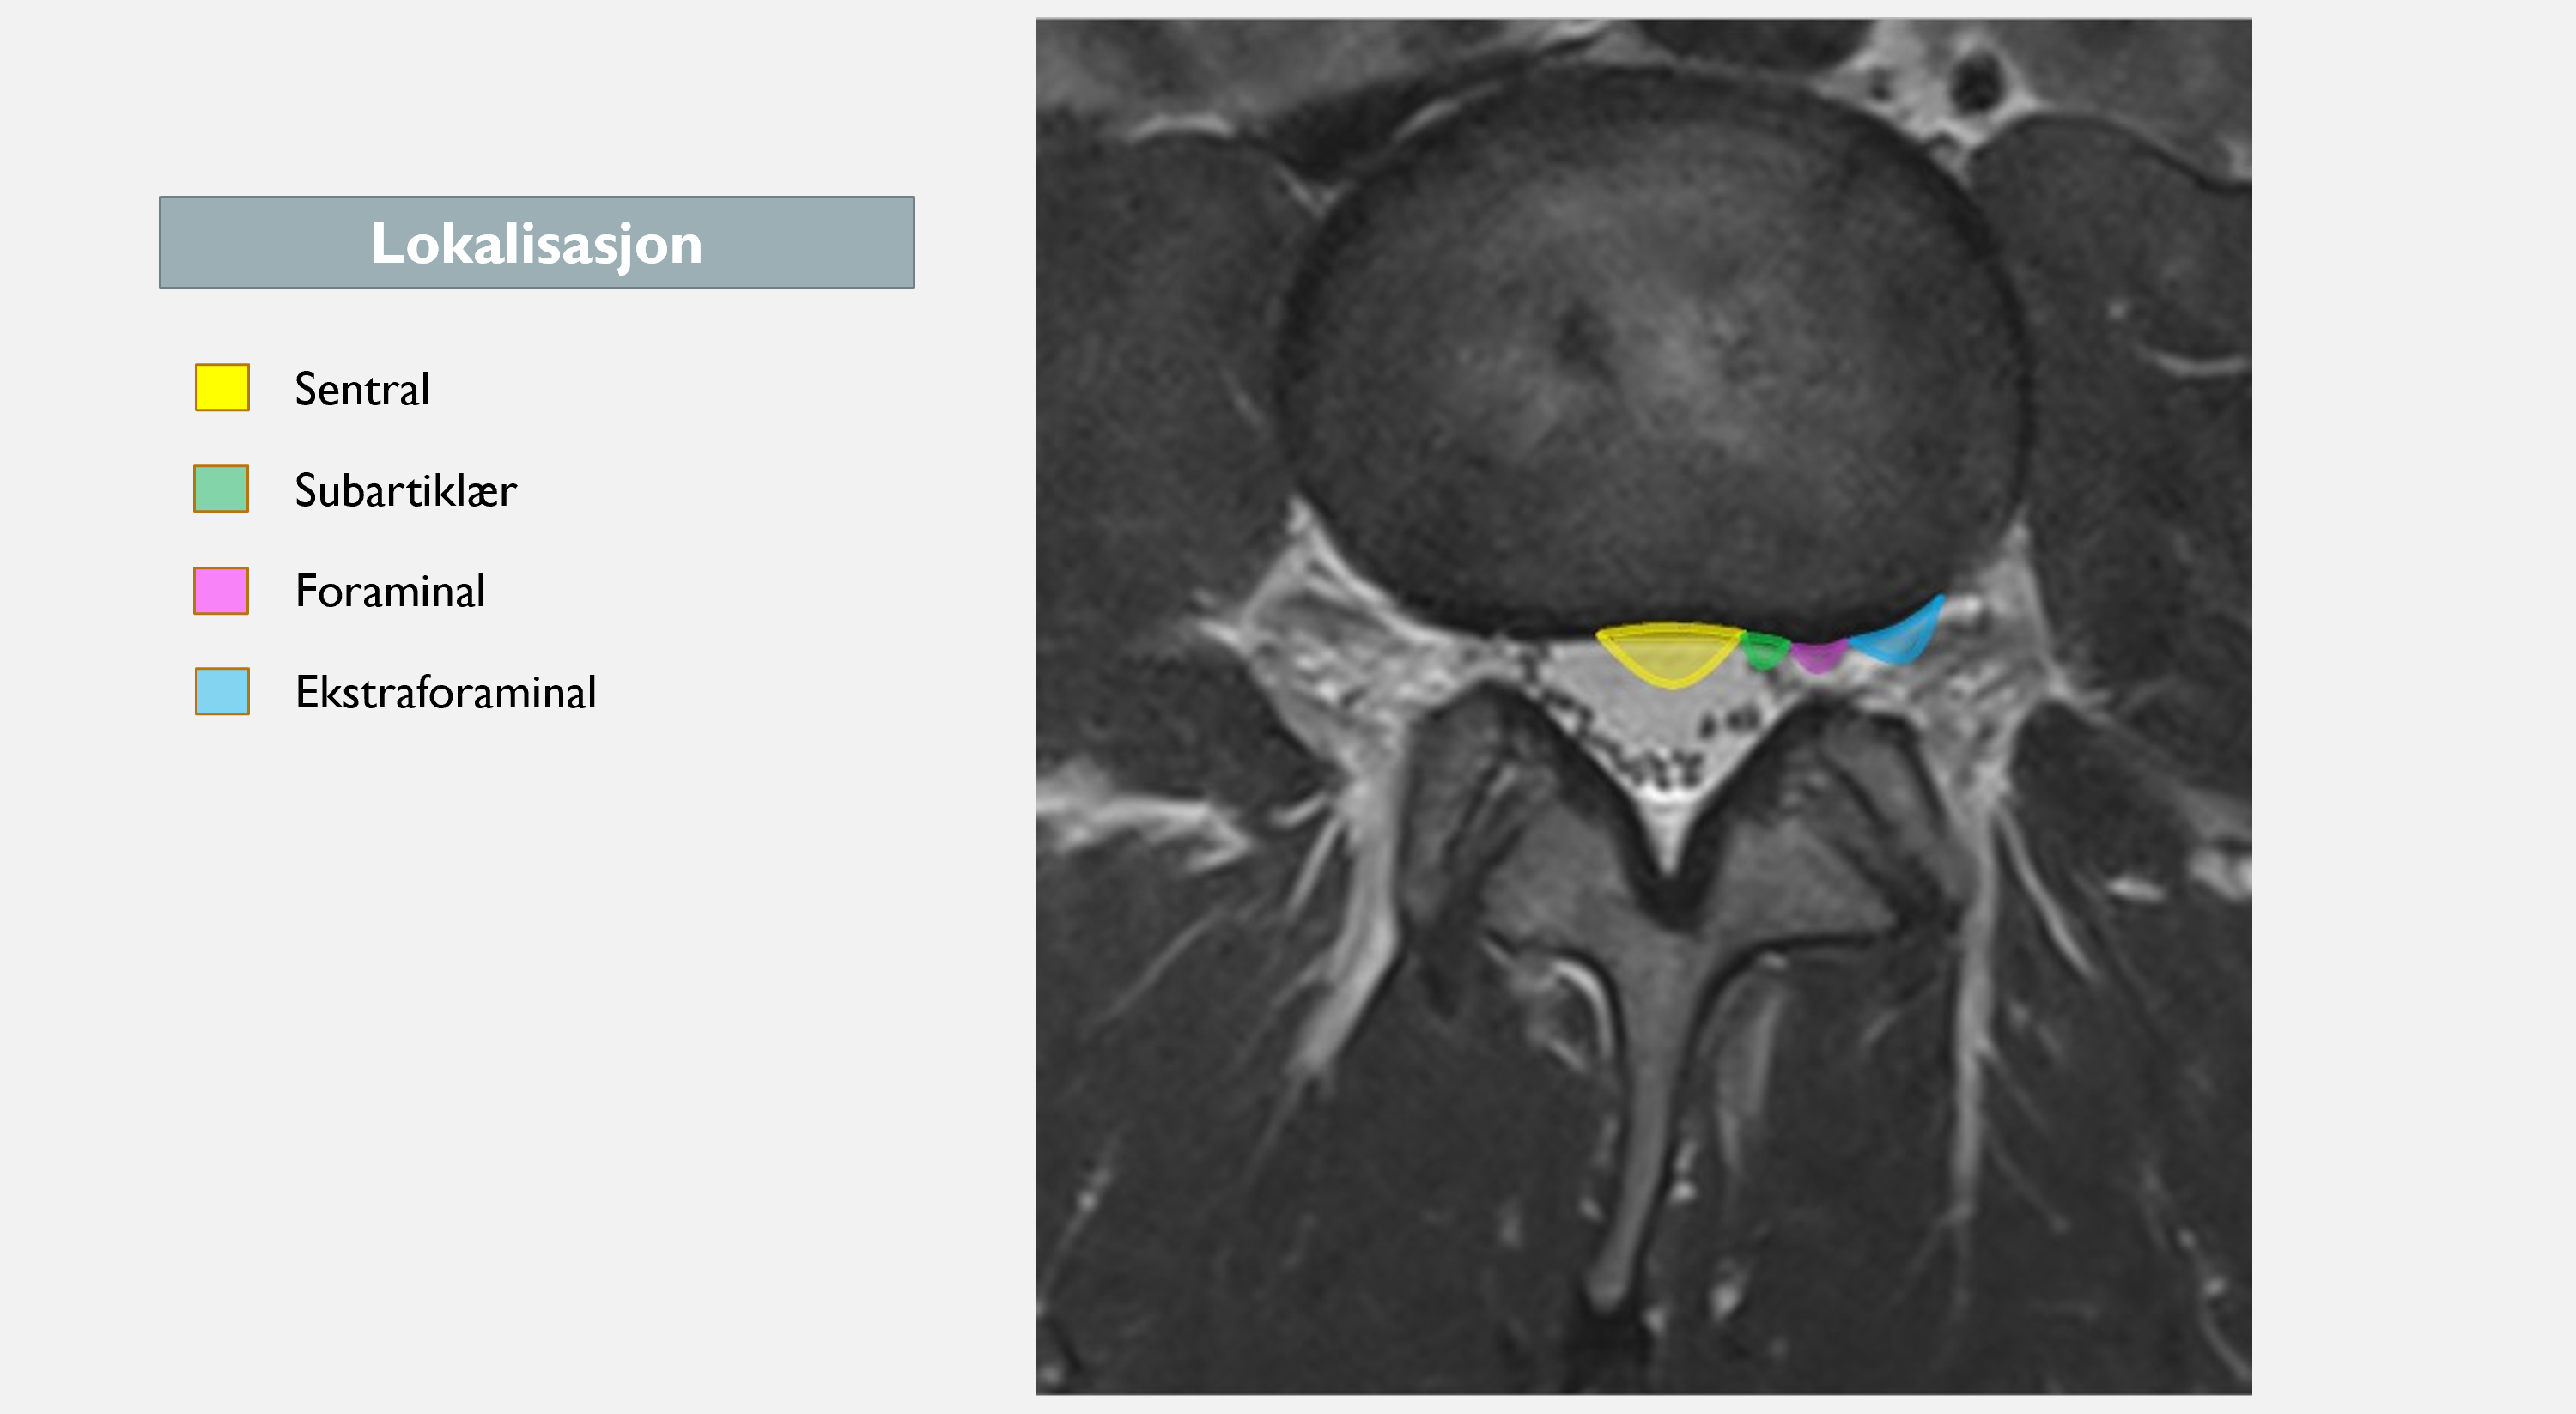

Har lokalisasjon noe å si for utfallet?

Vi vet at de fleste prolapser skjer subartikulært (3 av 4). I følge SPORT-studien er det dårligere prognose ved alle typer prolapser annet en subartikulært (18). Da tror jeg ikke man snakker om de sentrale prolapser, da disse sjeldnere gir plager (så lenge det ikke er en kjempestor prolaps som gir cauda equina syndrom). Man snakker da om de foraminale og ekstraforaminale prolapser. Pasientene med foraminal og ekstraforaminal prolaps kan ha et sterkere symptombilde, da skivemateriale kan trenge ut i en trangere kanal med begrenset plass til forskyvning av nerven. Spinalganglion til bakre horn befinner seg også her, som også er en potensielt smertesensitiv struktur (30,31). Det er også andre studier som viser at disse pasientene har noe dårligere resultater av både operasjon og konservativ behandling (32,33).